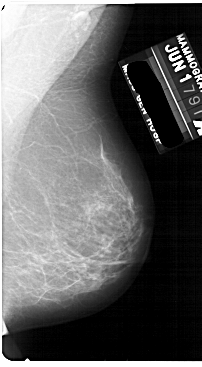

A_1870_1.RIGHT_MLO

RIGHT_MLO LINES 5491 PIXELS_PER_LINE 3016 BITS_PER_PIXEL 12 RESOLUTION 43.5 NON_OVERLAY